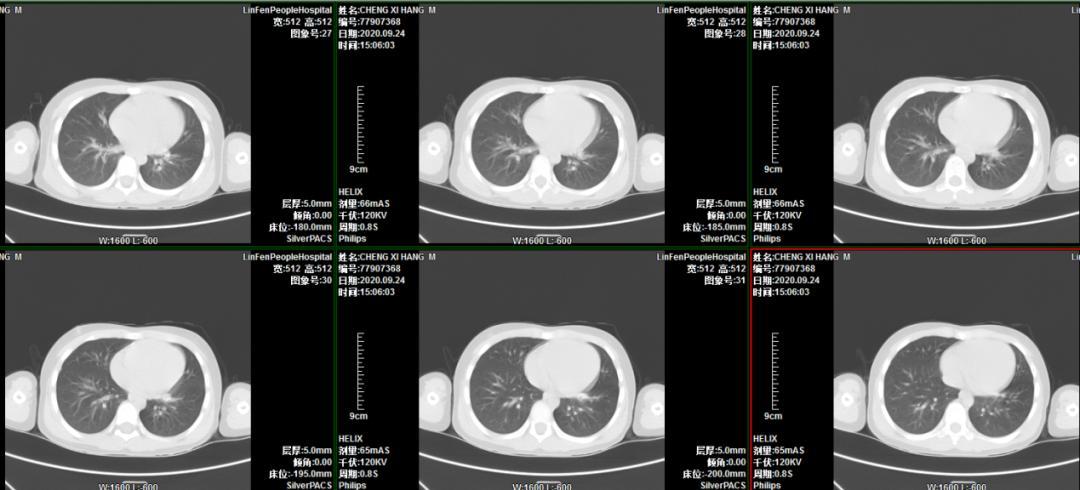

患儿程某,男,6岁3月,主因“间断咳嗽、喘息20天”入住我院普通儿科。入院后行胸部CT示左肺下叶不张,进一步增强扫描考虑左肺下叶支气管存在异物堵塞。考虑病程长,异物位于左肺下叶亚支,难度大。小儿呼吸科李荟主任积极邀请首都医科大学附属北京儿童医院呼吸儿科室杨海明主任、气管镜室李干主任亲临我院会诊指导,顺利进行了支气管镜检查及异物取出术,术后5天复查胸部CT肺不张完全恢复。

术后胸部CT